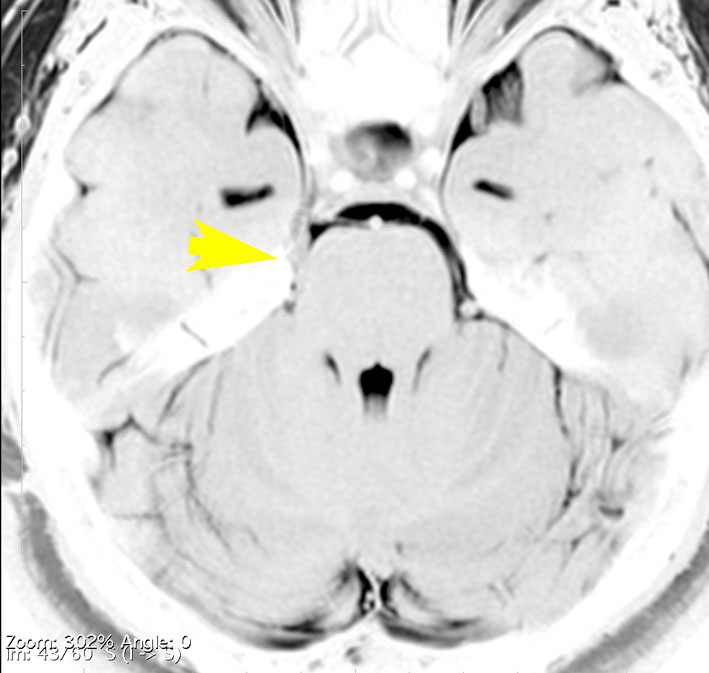

これは1989年に50歳で発症した左三叉神経痛の女性のMRIです。赤いのが類表皮のう胞という良性腫瘍で,黄色く塗ったのが左三叉神経です。腫瘍による圧迫で三叉神経がゆがんでいるのがよく解ります。2010年まで20年間,ほんの少しのカルバマゼピン(テグレトール)の服用で我慢できました。腫瘍は20年の間にゆっくり大きくなって,一時期は左の顔面けいれんもありました。2010年になって眼球運動障害による複視(ものが2重に見える)という症状が出て,年齢も70歳を越えたので開頭手術で腫瘍を摘出しました。術後は目の動きも正常になって三叉神経痛も消失しました。でも,類表皮のう胞の手術はリスクもあって簡単なものではありませんから,手術をすぐに勧める場合と,この患者さんの様にながーく経過を見る場合があります。判断は難しいものです。